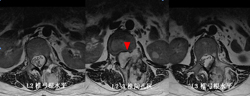

图3-1,CT矢状面和冠状面重建,显示病变为成骨性,病变内有点状钙化。

图3-2,CT横断面显示病变累及L2-L3水平椎骨。

图3-3,MRI矢状面及冠状面显示病变侵入椎管明显压迫硬膜囊和马尾神经

图3-4,MRI横断面显示病变存在软组织成分,在左侧L2-3椎间孔区肿瘤累及椎管内外,明显压迫马尾神经,并且包绕左侧L2神经根。